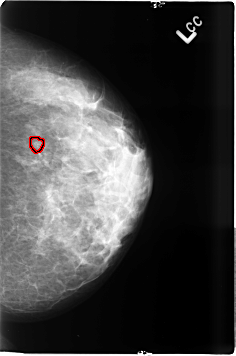

ics_version 1.0 filename B-3497-1 DATE_OF_STUDY 20 5 1998 PATIENT_AGE 38 FILM FILM_TYPE REGULAR DENSITY 3 DATE_DIGITIZED 8 6 1999 DIGITIZER LUMISYS LASER SEQUENCE LEFT_CC LINES 4624 PIXELS_PER_LINE 3056 BITS_PER_PIXEL 12 RESOLUTION 50 OVERLAY LEFT_MLO LINES 4640 PIXELS_PER_LINE 3072 BITS_PER_PIXEL 12 RESOLUTION 50 OVERLAY RIGHT_CC LINES 4600 PIXELS_PER_LINE 3032 BITS_PER_PIXEL 12 RESOLUTION 50 NON_OVERLAY RIGHT_MLO LINES 4600 PIXELS_PER_LINE 3008 BITS_PER_PIXEL 12 RESOLUTION 50 NON_OVERLAY |

FILE: B_3497_1.LEFT_CC.OVERLAY TOTAL_ABNORMALITIES 1 ABNORMALITY 1 LESION_TYPE CALCIFICATION TYPE PLEOMORPHIC-AMORPHOUS DISTRIBUTION CLUSTERED ASSESSMENT 4 SUBTLETY 3 PATHOLOGY BENIGN TOTAL_OUTLINES 1 BOUNDARY |